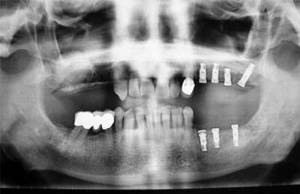

Implantes dentales, inclusiones dentarias (caninos incluidos y cordales o muelas del juicio), quistes y tumoraciones de los maxilares, boca, cabeza y cuello, cirugía de los tejidos blandos de la boca (làser de CO2), patología y cirugía de las encías (periodoncia), cáncer de la boca, deformidades dentofaciales, traumatismos de la boca y de la cara, patología de las glándulas salivares.

Existen muchas técnicas y patologías que pueden incluirse en esta especialidad, pero destacaremos algunas de las más importantes: